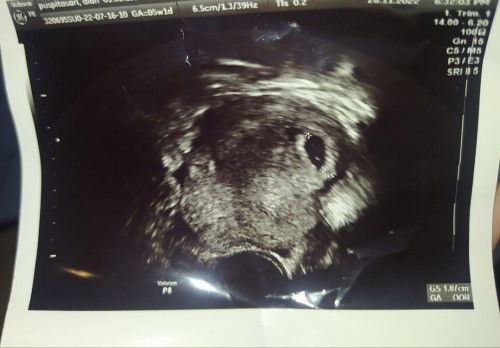

Usg 5week apakah normal

bun, usg uk 5w1d ukuran kantong segini tu normal kan yaa. mohon doanya, kehamilan ke tiga saya setelah 2 kali di tahun lalu keguguran. semoga kehamilan kali ini sehat2 tumbuh kembangnya sempurna, lancar sampe lahiran. aamiin

Bun aku juga sama USG kehamilan 5week emg segitu